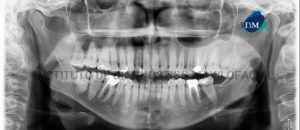

Paciente masculino de 64 años acude al Instituto de Diagnóstico Maxilofacial para la evaluación imagenológica de control. A la evaluación de la radiografía panorámica se